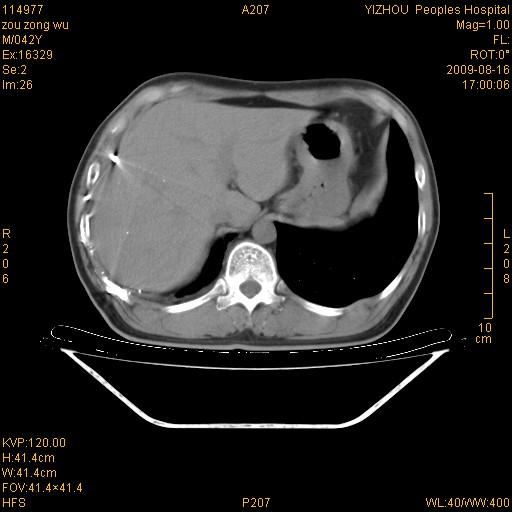

以下是引用zjzjr在2009-8-17 10:42:00的发言:[br]右侧间质性肺炎伴纤维化,右肺下叶肺囊肿伴感染(不除外外伤后引起),右肺野及胸壁软组织\\肝内见多发斑点状,中枪了吧.右侧胸膜肥厚\\粘连.